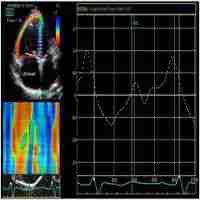

| Abstract | Providing prognostic information is important when counselling patients and planning treatment strategies in chronic thromboembolic pulmonary hypertension (CTEPH). The aim of this study was to assess the prognostic value of gold standard imaging of cardiac structure and function using cardiac magnetic resonance imaging (CMR) in CTEPH. Consecutive treatment-naive patients with CTEPH who underwent right heart catheterization and CMR between 2011 and 2017 were identified from the ASPIRE (Assessing-the-Specturm-of-Pulmonary-hypertensIon-at-a-REferral-centre) registry. CMR metrics were corrected for age and sex where appropriate. Univariate and multivariate regression models were generated to assess the prognostic ability of CMR metrics in CTEPH. 375 patients (mean+/-standard deviation: age 64+/-14 years, 49% female) were identified and 181(48%) had pulmonary endarterectomy (PEA). For all patients with CTEPH, left-ventricular-stroke-volume-index-%predicted (LVSVI%predicted) (p=0.040), left-atrial-volume-index (LAVI) (p=0.030), the presence of comorbidities, incremental shuttle walking test distance (ISWD), mixed venous oxygen saturation and undergoing PEA were independent predictors of mortality at multivariate analysis. In patients undergoing PEA, LAVI (p<0.010), ISWD and comorbidities and in patients not undergoing surgery, right-ventricular-ejection-fraction-%predicted (RVEF%pred) (p=0.040), age and ISWD were independent predictors of mortality. CMR metrics reflecting cardiac function and left heart disease have prognostic value in CTEPH. In those undergoing PEA, LAVI predicts outcome whereas in patients not undergoing PEA RVEF%pred predicts outcome. This study highlights the prognostic value of imaging cardiac structure and function in CTEPH and the importance of considering left heart disease in patients considered for PEA. |